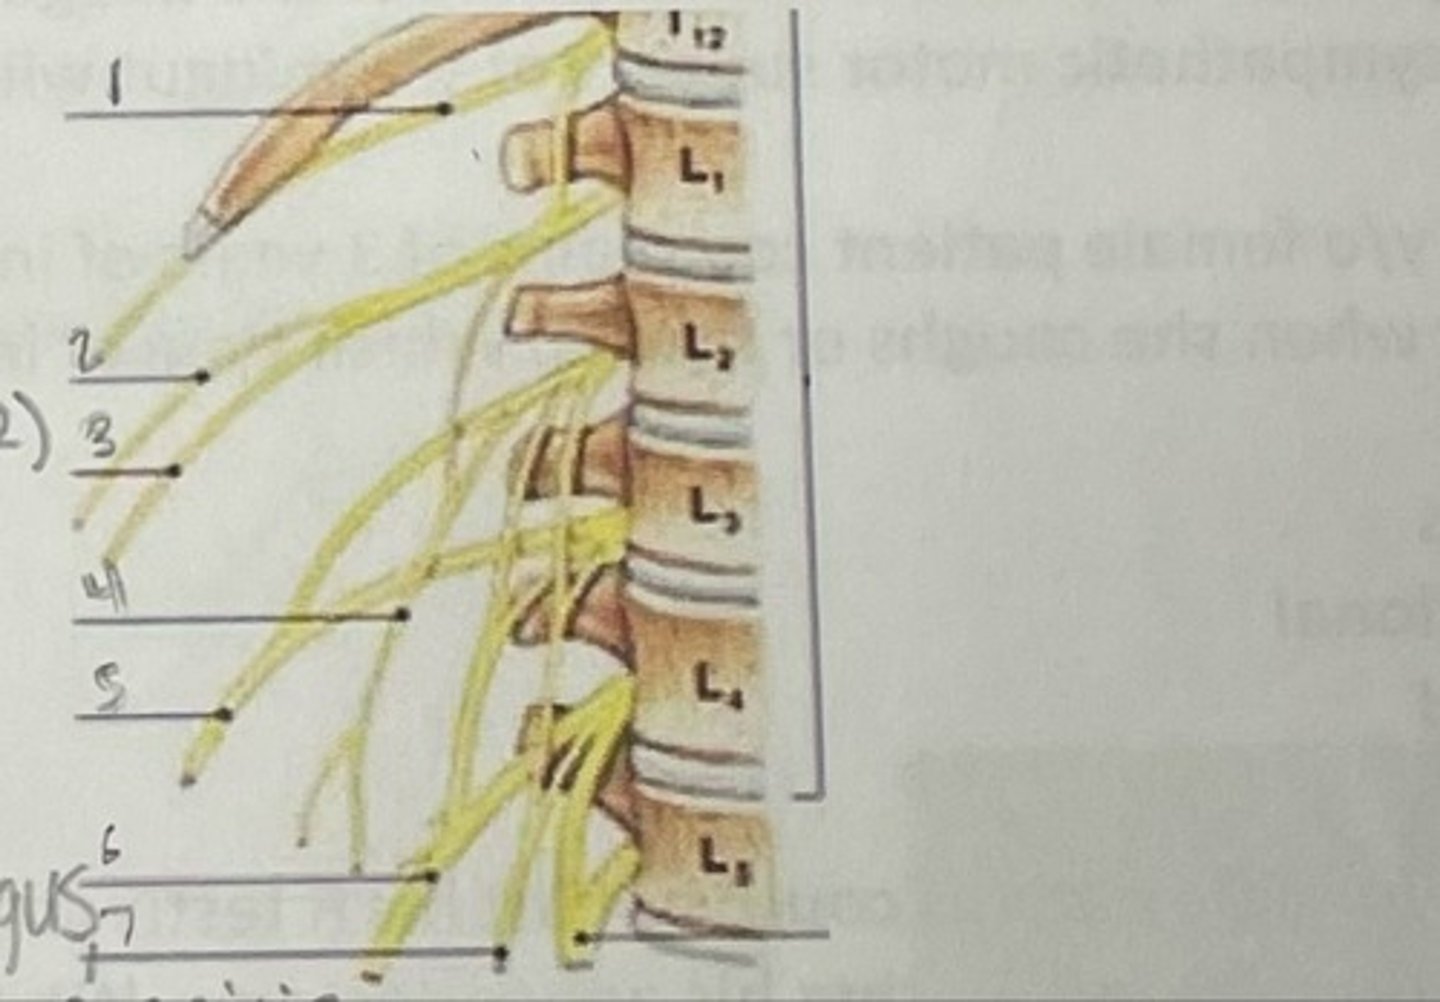

Subcostal nerve (T12)

What is 1

Illiohypogastric nerve (T12/L1)

What is 2

Illioinguinal nerve (L1)

What is 3

Genitofemoral nerve (L1-L2) ; on top of psoas

What is 4

lateral femoral cutaneous nerve (L2-L3)

What is 5

Femoral Nerve (L2-L4)

What is 6

Obturator nerve (L2-L4)

What is 7